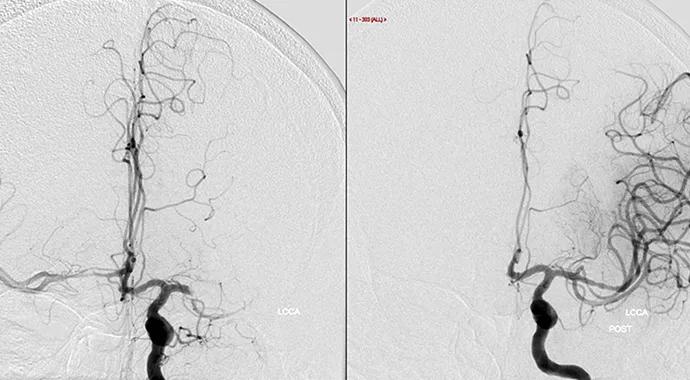

large vessel occlusion before and after treatment

Outcomes are good for adults aged 18 to 49 years with large vessel occlusion acute ischemic stroke (LVO-AIS), irrespective of etiology. The exception is large artery atherosclerosis (LAA), which is associated with worse stroke scores on discharge.